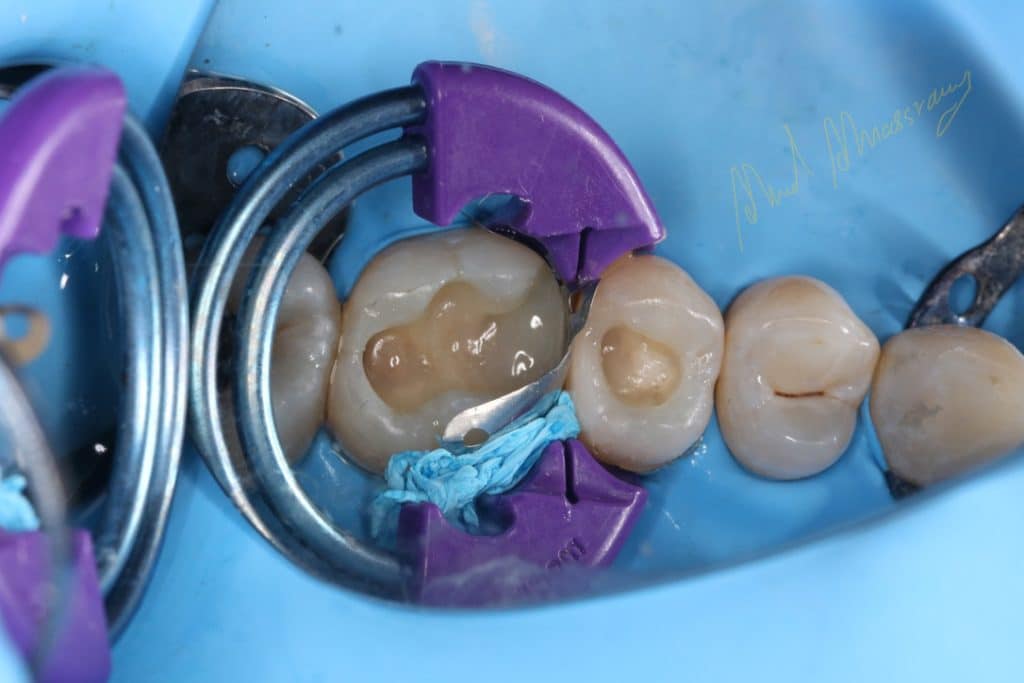

immediate dentin sealing(IDS)

Bioclear matrix system

sixth generation se bond